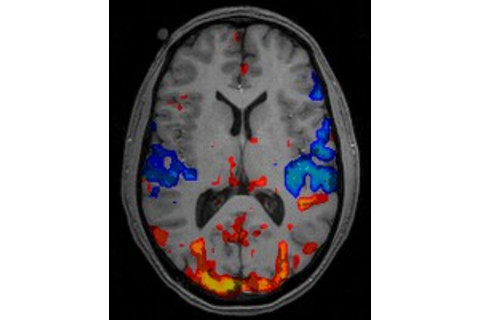

The problem, they say, is that in studying brain activations, neuroscientists have been overly focussed on statistical significance. In a typical fMRI experiment, the researchers look for clusters (aka 'blobs') of brain activation, defined as areas where the observed activity is unlikely to have occured by chance (p < 0.05). These clusters then get reported (and colorfully depicted) in the paper. But the actual magnitude of the neural response is rarely considered. A small but consistent effect would produce just the same blob as a large but variable activation.